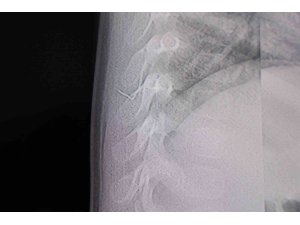

Alınan bilgiye göre, Kahramanmaraş'ta farklı ortopedi, çocuk cerrahisi ve beyin cerrahisi kliniklerine başvurusu yapılan bir yaşındaki bebeğin, sırt bölgesinde yabancı bir cisim olduğu ancak müdahalenin zor olduğu ve 8 yaşına kadar beklenmesi gerektiği bildirildi. Aile, bebekleri için son olarak HG Hospital'e başvurdu. HG Hospital Beyin ve Sinir Cerrahisi Uzmanı Prof. Dr. İdris Altun tarafından yapılan tetkiklerde, yabancı cismin cilt altında, omurilik kanalına yakın bir bölgede olduğu ve akciğer zarına doğru ilerlediği belirlendi. Hasta, genel anesteziye alınmadan, lokal anestezi ve sedasyon eşliğinde ameliyata alındı. Yapılan müdahalede yabancı cisim tamamen çıkarıldı. Çıkarılan cismin, ince zımba teline benzer metal bir tel olduğu ve yaklaşık 2 santimetre uzunluğunda bulunduğu tespit edildi. Hasta, aynı gün taburcu edildi.

Konuya ilişkin açıklama yapan Prof. Dr. İdris Altun, "Sırtında yabancı bir cisim olduğu söylenmiş ancak çıkarılamayacağı ve 8 yaşına kadar beklenmesi gerektiği ifade edilmişti. Bize başvurduğunda yaptığımız tetkiklerde, cilt altında, omurilik kanalına çok yakın ve akciğer zarına doğru ilerleyen bir yabancı cisim tespit ettik. Hastamızı tamamen uyutmadan, lokal anestezi ve sedasyon eşliğinde müdahale ederek lezyonu tamamen çıkardık. Çıkardığımız cismin ince zımba teline benzer, yaklaşık 2 santimetre uzunluğunda metal bir tel olduğunu gördük. Bu yabancı cisim alınmasaydı, bölgede enfeksiyon gelişebilirdi. Enfeksiyon sonucu omurilik kanalında ciddi hasarlar oluşabilir, çocuk büyüdükçe cismin hareket etmesine bağlı olarak omurilikte zedelenmeler meydana gelebilirdi. Ayrıca yana doğru ilerleyerek akciğer zarına ve akciğere batma riski vardı. Bu da enfeksiyona ve ilerleyen süreçte tümörle karışabilecek tablolara neden olabilirdi. Şu an hastamız gayet sağlıklı. Gerekli kontrolleri yaptık ve aynı gün taburcu ettik" dedi.